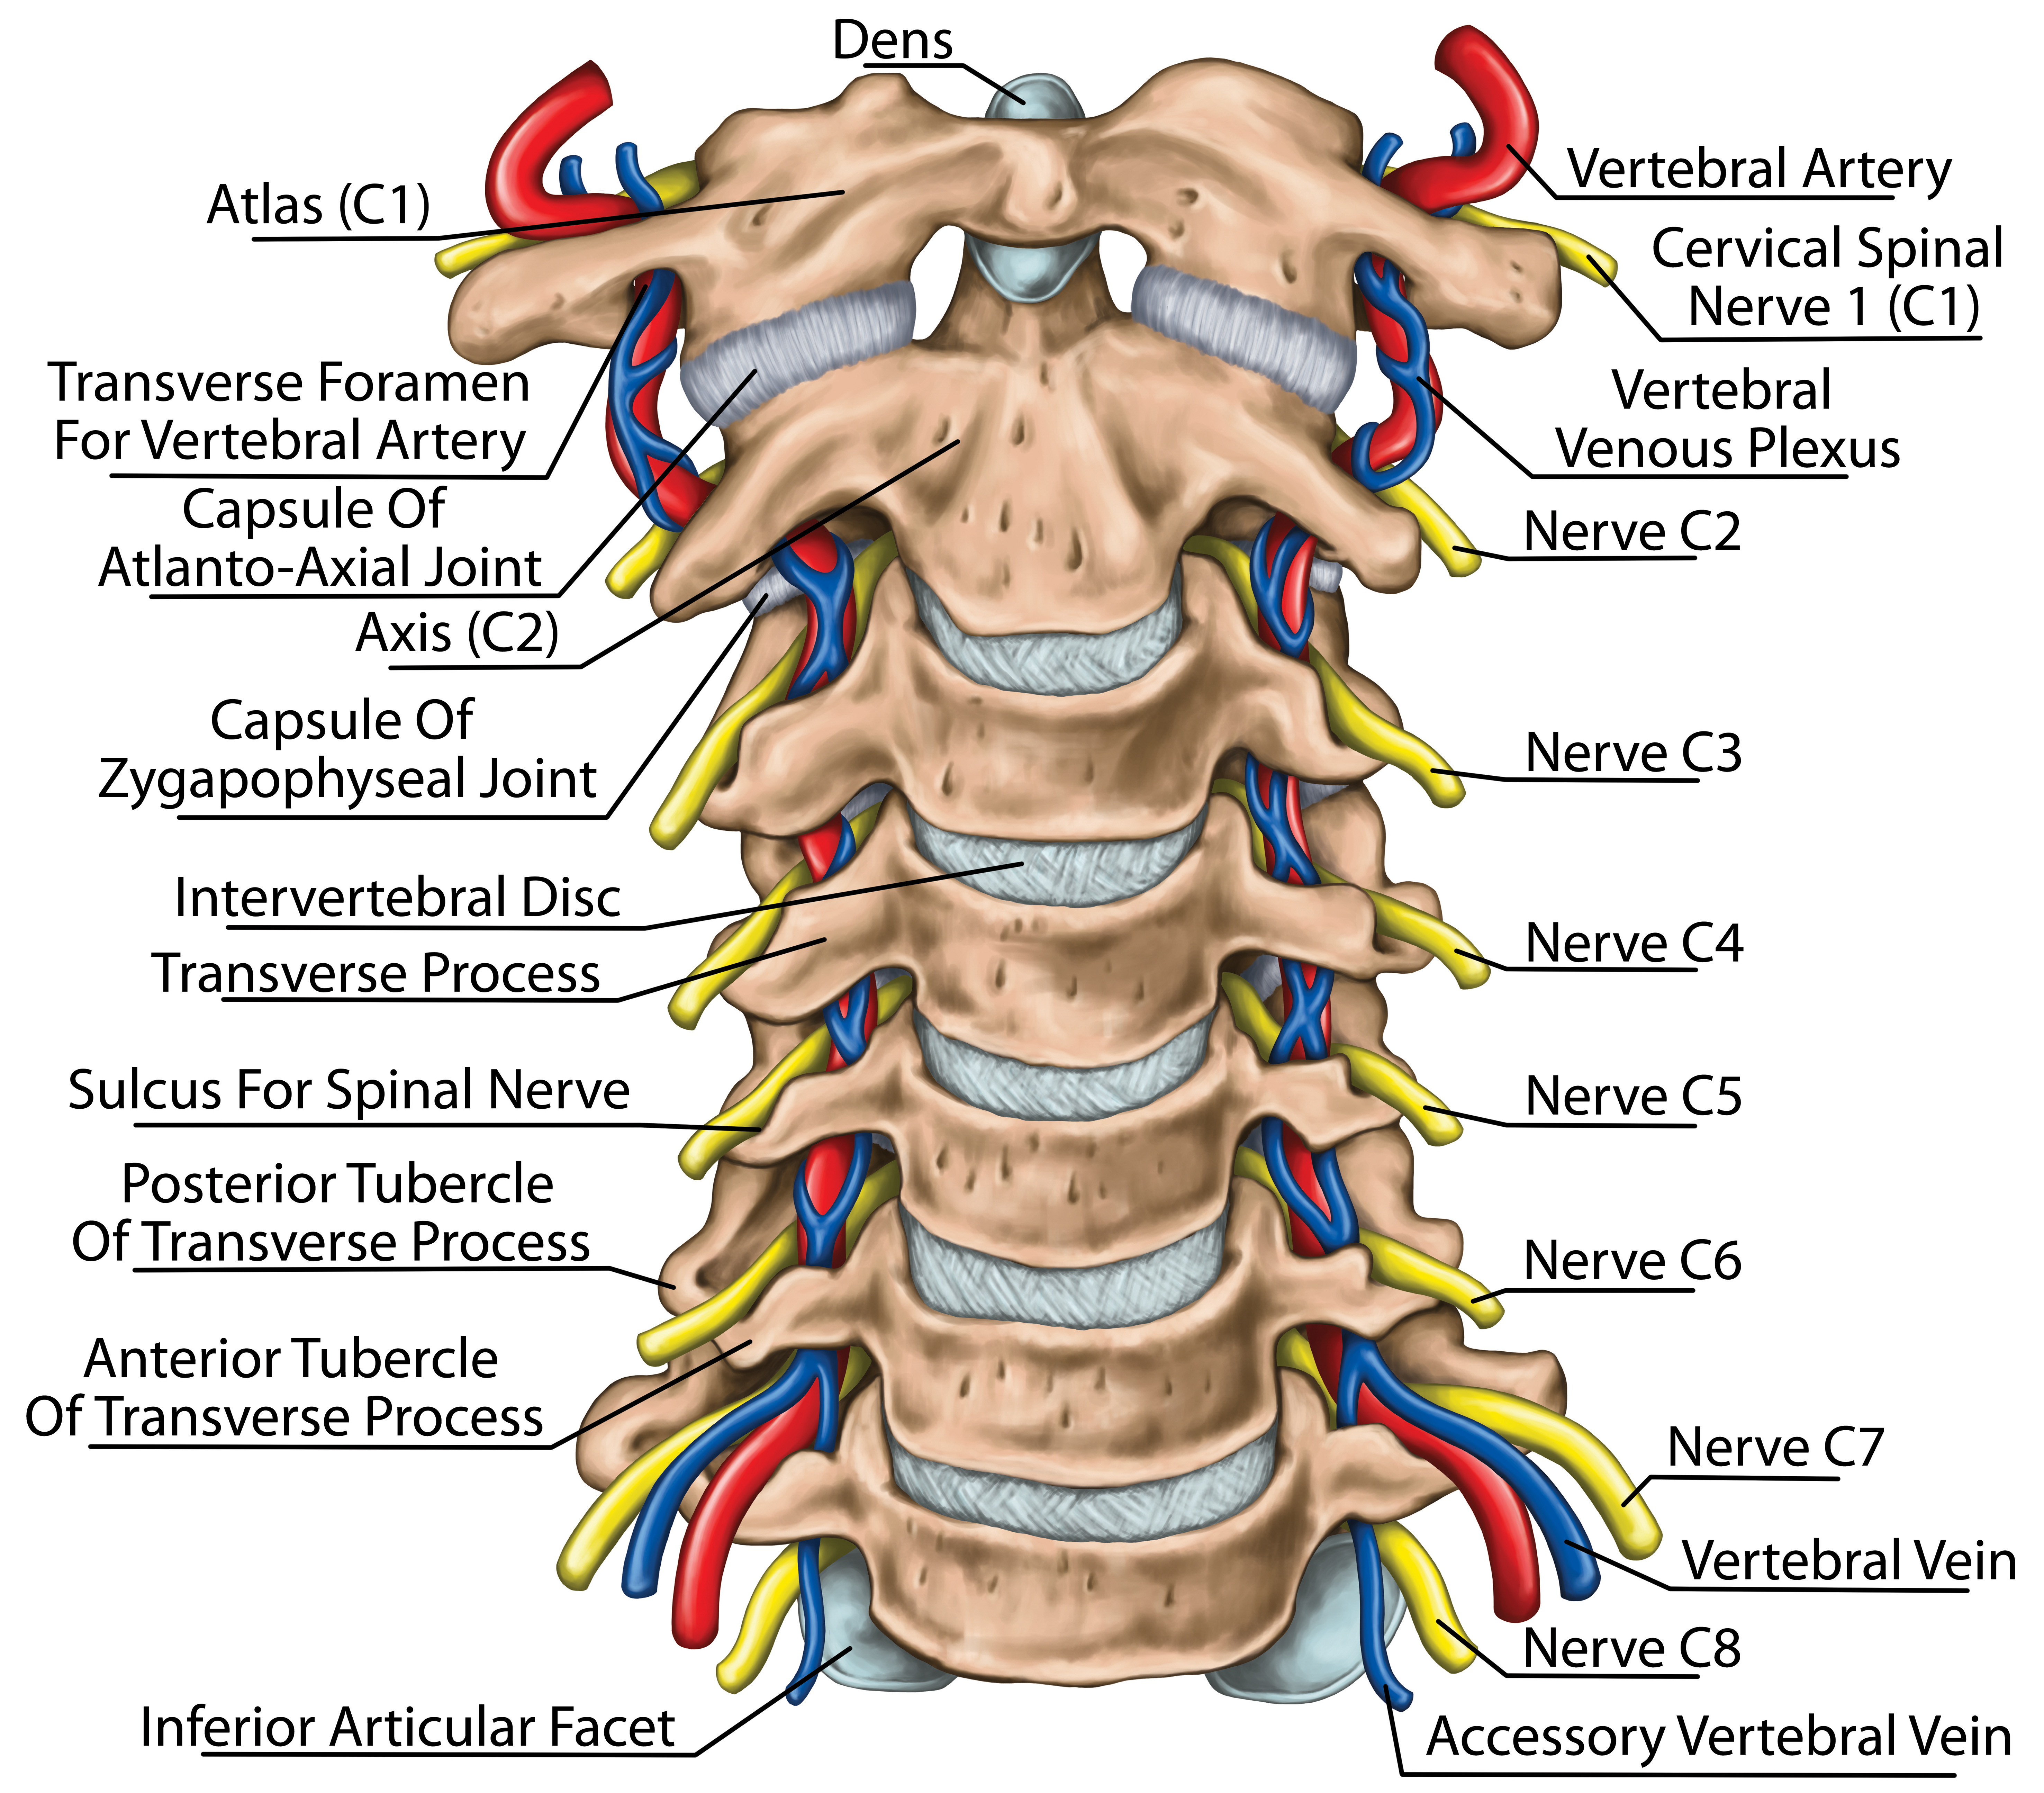

cervical nerves

C1-C8 (8 pair)

cervical plexus

C1-C4

major nerve: phrenic nerve

brachial plexus

C5-T1

segmental branches

hypoglossal nerve (12)

lesser occipital nerve

greater auricular nerve

transverse cervical nerve

ansa cervicalis

accessory nerve (11)

phrenic nerve

supraclavicular nerves